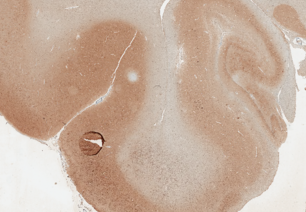

The overarching goal of our clinical research is to use a neuropathological approach (human tissue based) to identify changes in the brain that can be correlated with clinical, genetic, transcriptomic and other measures to identify mechanisms contributing to neurodegenerative tauopathies, a group of related disorders including Alzheimer’s. The clinical laboratory is rooted in “classical” neuropathology, a methodical albeit laborious approach involving extensive clinical case reviews alongside manual examination of brain tissues under the microscope, often with the same methods that the founders of the field used, such as the silver stains pioneered by Alois Alzheimer over 100 years ago. Careful microscopic observation is remarkably powerful when correlated with clinical symptomatology, and has enabled us to define new diagnostic categories and staging systems, including the first description of primary age-related tauopathy. We have been deeply involved with efforts to define criteria for other tauopathies, including chronic traumatic encephalopathy, aging-related tau astrogliopathy, and progressive supranuclear palsy. These studies have been done in a highly collaborative spirit, leveraging a large international network of neuropathologists working closely together, sharing tissues and ideas. These projects, which depend, on input and knowledge from many investigators, have reinforced our respect for the collective wisdom of the neuropathology clinical research community and how it forms the foundation for transformational conceptual innovation. Well-characterized human tissues, imbued with the knowledge of expert pathologists, combined with cutting edge technological innovations is a potent force for discovery - a strategy we use to uncover novel associations and candidate disease mechanisms. Our genetic studies, transcriptomic studies, stem cell models, and now computer vision/deep learning models have been our springboard to launch off the foundation we built using classical neuropathology. New emerging unpublished work from our team highlights innate immunity and oligodendrocyte dysfunction in tauopathy. Once again, these projects are highly collaborative: we work closely with the Tau Consortium, the Progressive Supranuclear Palsy (PSP) genetics consortium, and a group that we founded, the primary age-related tauopathy working group.

CLINICAL PATHOLOGY & DIAGNOSTIC BIOMARKERS